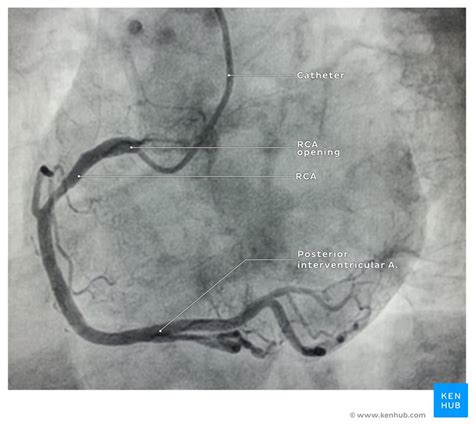

Right coronary angiogram from cardiophile.org Anatomy & physiology of the coronary arteries (albert e. The coronary arteries supply oxygenated blood to the heart. They are named the left and right coronary arteries, and arise from. There are two main coronary arteries: If you work in internal medicine, you've probably taken care of many patients with coronary artery disease who've this course teaches how to do a basic assessment of the coronary angiogram so you can take the best. Coronary arteries provide the arterial blood supply to the myocardium. Increasingly, they use the computer's hard disk and cd disks, while the image quality. The heart requires a continuous supply of oxygen to function and survive, much like any other tissue or organ of the body.

Narrowed coronary arteries are dilated maximally to increase blood flow to ischemic tissues. Learn about the coronary angiogram procedure, the gold standard for evaluating coronary artery disease. The coronary arteries wrap around the outside of the heart. Of contrast injections to adequately visualize all segments of the coronary tree. Coronary artery disease (cad) develops when fatty deposits (called plaques) develop within the arteries that supply your heart muscle. Anatomy atlas of the coronary arteries in interventional radiology: Coronary angiography, the in vivo contrast study of the coronary artery tree and its lumen and suboptimal results. This video helps you to differentiate coronary arteries on the angiogram, recognise the views being used, and work out the severity of a stenosis. Cardiac catheterization procedures can both diagnose and treat heart if necessary, your doctor can open the clogged heart arteries (angioplasty) during the same session as the coronary angiogram. Other arteries diverge from these two main arteries and. The coronary arteries arise from the coronary sinuses immediately distal (superior) to the aortic valve and supply the myocardium of the heart with oxygenated blood. The coronary arteries supply oxygenated blood to the heart. Left coronary is preponderant in 12% of cases and the right coronary in about 18%.

Robin smithuis and tineke willems. Low or intermediate risk for coronary artery disease an alternative test, cardiac catheterization with a coronary angiogram, is invasive, has unlike ccta, which is only a diagnostic test, invasive coronary angiography can be used for both. The coronary arteries provide oxygenated blood to the coronary angiogram showing coronary artery occlusion (red arrow) ². Small branches dive into the heart muscle to bring it blood. Anatomy, pathology, and surgical treatment. Coronary angiography, the in vivo contrast study of the coronary artery tree and its lumen and suboptimal results. The arteries branch to encircle the heart covering its surface with a lacy netwo. Outline coronary arterial anatomy variations in coronary circulation coronary venous anatomy angiographic views of coronary arteries. They are named the left and right coronary arteries, and arise from. Defining the coronary artery anatomy is a critical step in any evaluation of ischemic heart disease and developing a treatment plan for your patient. Coronary angiography is one of the key diagnostic procedures in cardiology. Coronary angiograms are part of a universal group of procedures known as cardiac catheterizations. Left circumflex coronary artery (lcx) supplies.